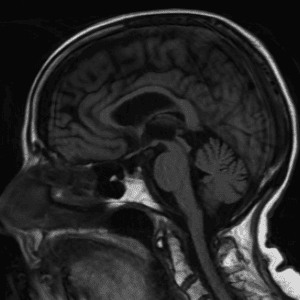

Neurodegenerative Diseases